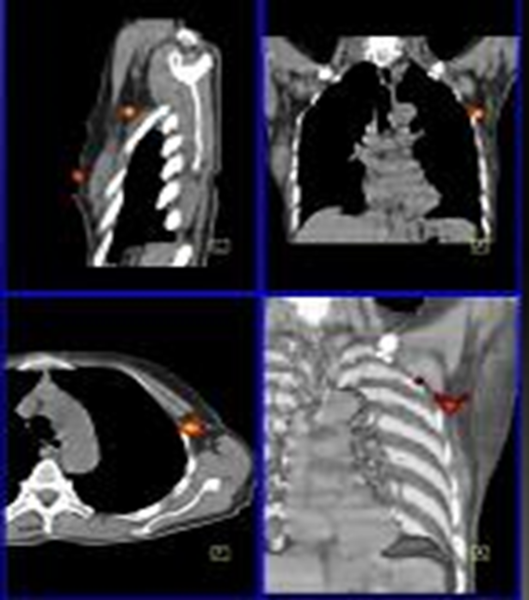

Figure 5 - Cancer du sein : ganglion sentinelle localisé par SPECT/CT